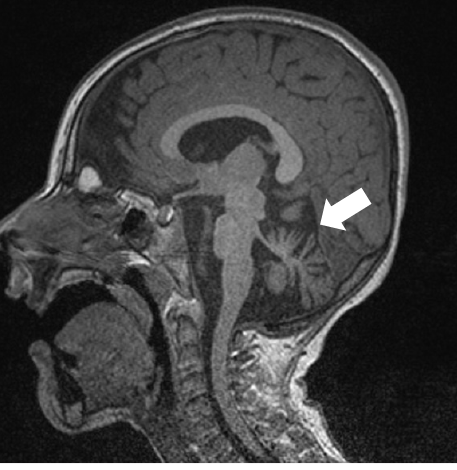

La resonancia magnética de un paciente de 4 años con una mutación en el gen CHRM1 muestra una atrofia del cerebelo (flecha).

Por otro lado, Raúl Estévez y Alfons Macaya, del Grupo Clínico Vinculado al CIBERER en el Hospital Vall d’Hebron, han liderado un estudio publicado en la revista Human Mutation que ha identificado mutaciones en pacientes con problemas del desarrollo cerebral en el gen CHRM1, que codifica para el receptor muscarinico M1. El análisis de una de las mutaciones ha mostrado que el receptor mutado presenta una activación defectiva de sus vías de señalización. Estos datos sugieren que una reducción en la señalización muscarínica afecta el desarrollo cerebral.